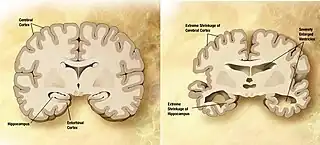

| Normal brain on left contrasted with structural changes shown in brain on right of person with Alzheimer's disease, the most common neurodegenerative disease[1] | |

Alzheimer's disease

Alzheimer's disease (AD) is a chronic neurodegenerative disease that results in the loss of neurons and synapses in the cerebral cortex and certain subcortical structures, resulting in gross atrophy of the temporal lobe, parietal lobe, and parts of the frontal cortex and cingulate gyrus.[11] It is the most common neurodegenerative disease.[1] Even with billions of dollars being used to find a treatment for Alzheimer's disease, no effective treatments have been found.[12] However, clinical trials have developed certain compounds that could potentially change the future of Alzheimer's disease treatments.[13] Within clinical trials stable and effective AD therapeutic strategies have a 99.5% failure rate.[14] Reasons for this failure rate include inappropriate drug doses, invalid target and participant selection, and inadequate knowledge of pathophysiology of AD. Currently, diagnoses of Alzheimer's is subpar, and better methods need to be utilized for various aspects of clinical diagnoses.[15] Alzheimer's has a 20% misdiagnosis rate.[15]